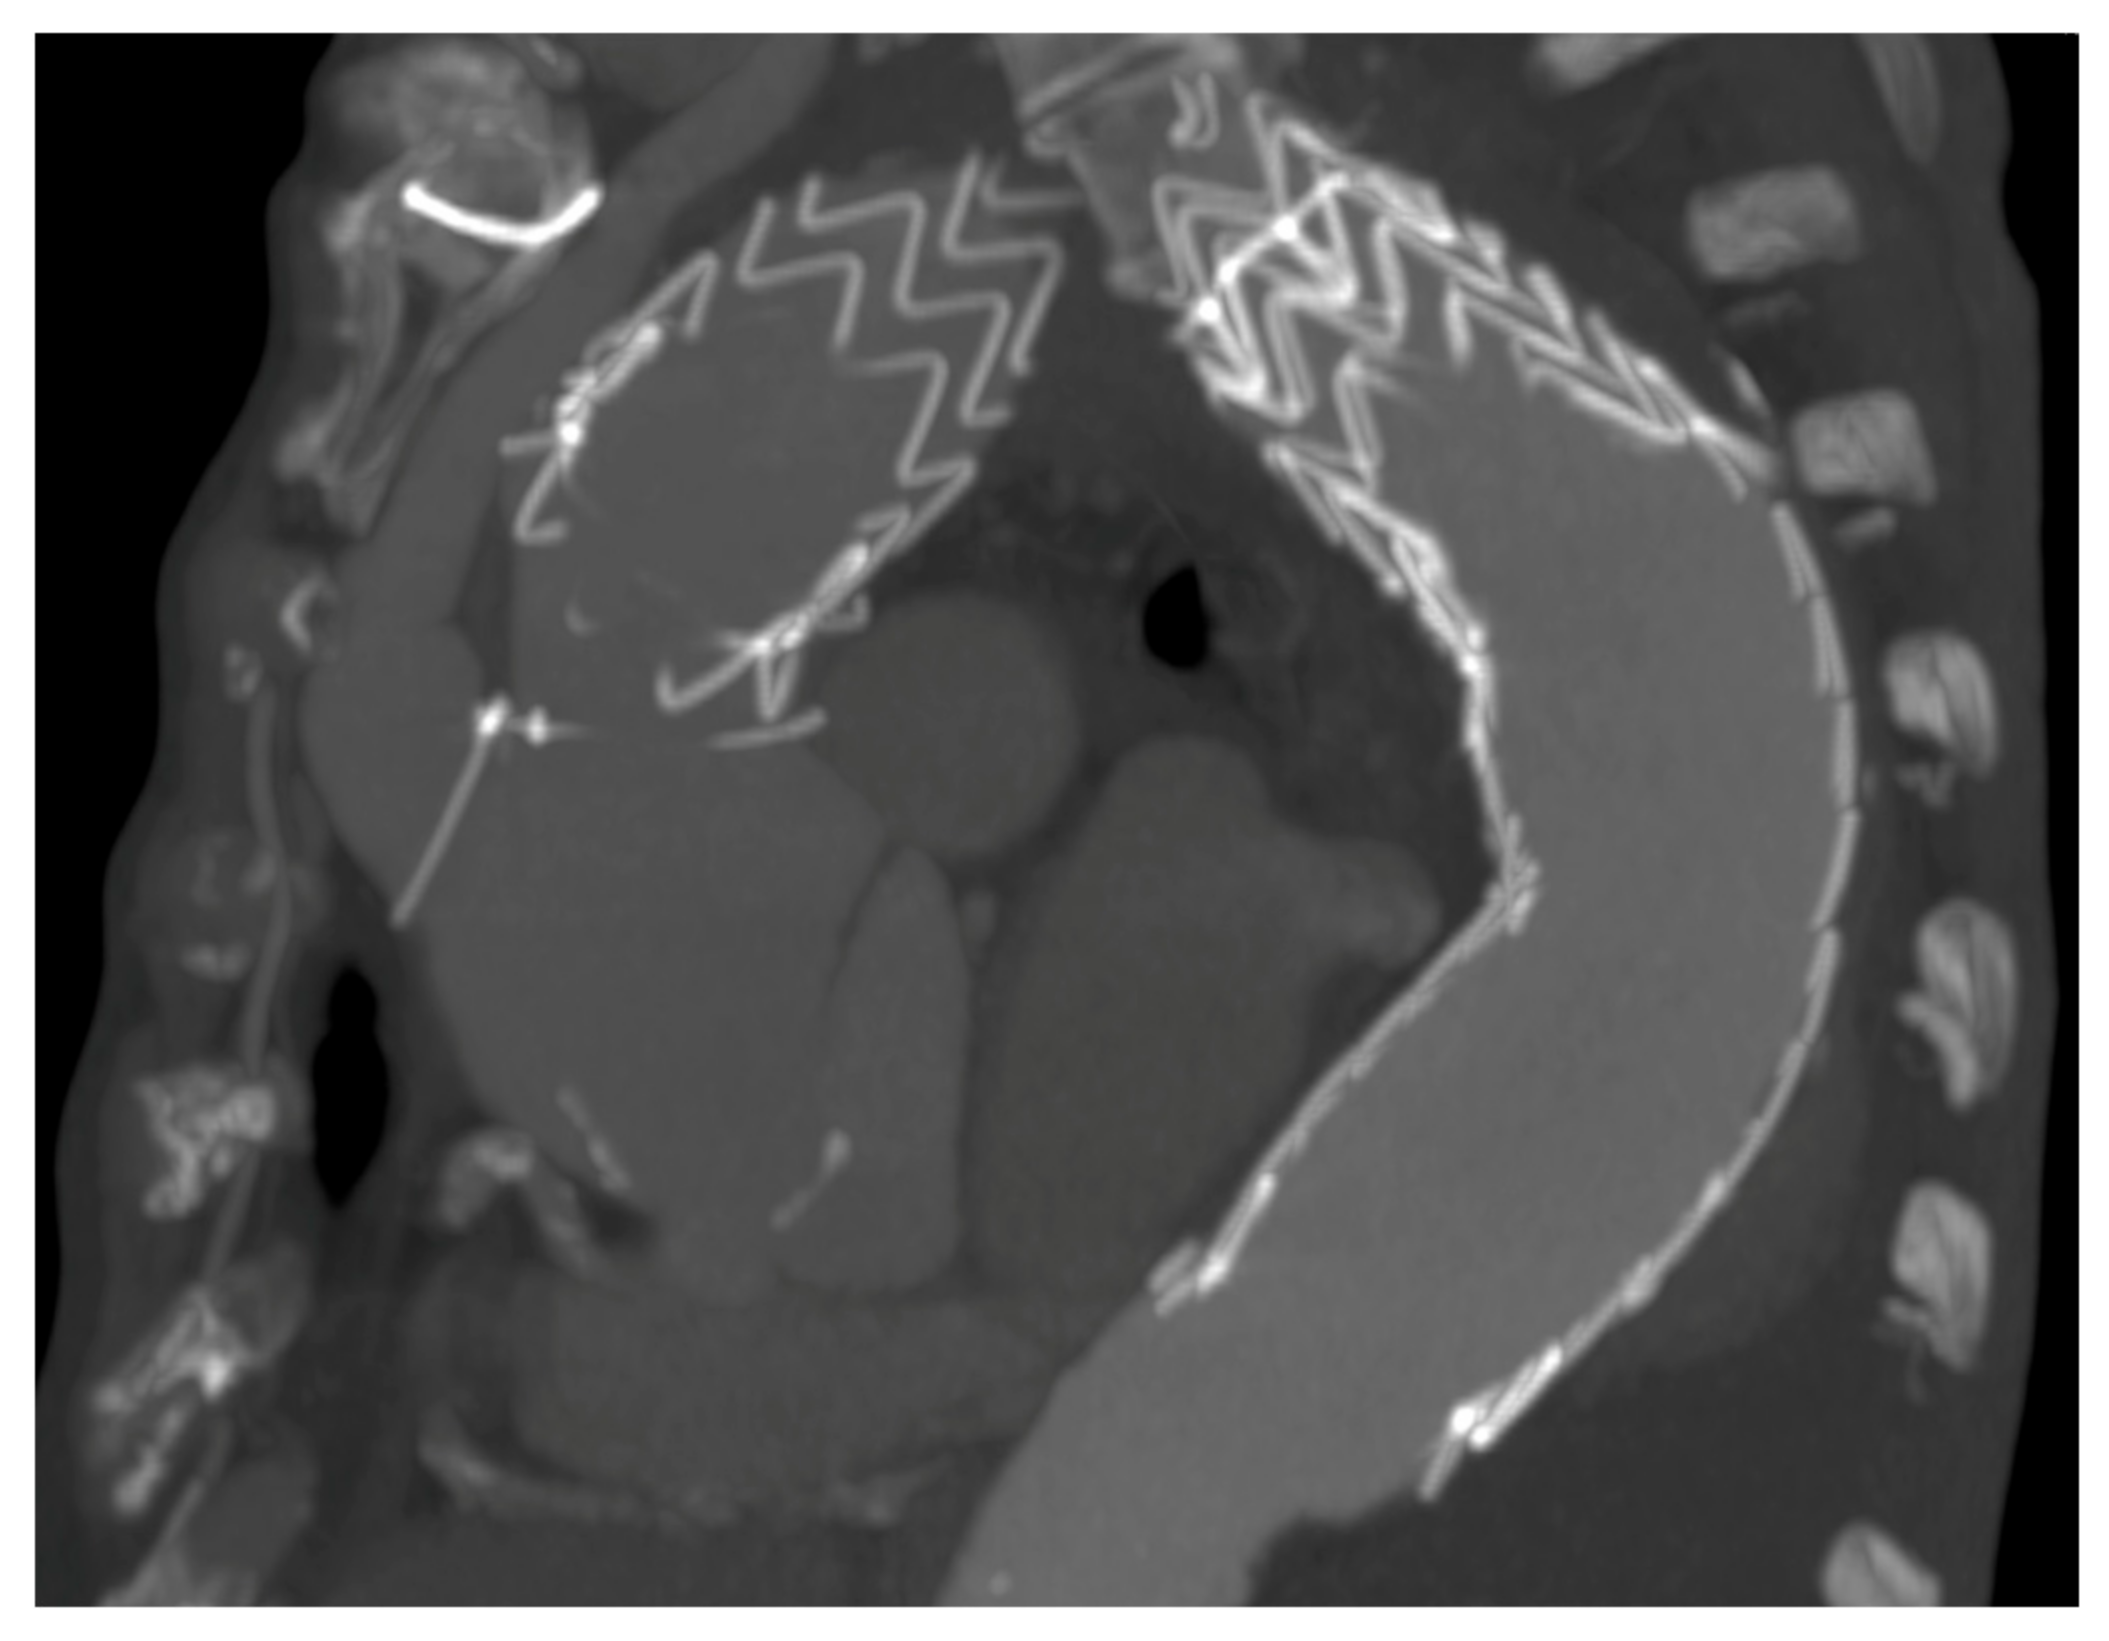

2.6. Radiopaque Markers

2.7. Endovascular Technique

| TEVAR flair and bulging (treated) | 1 | 3 |